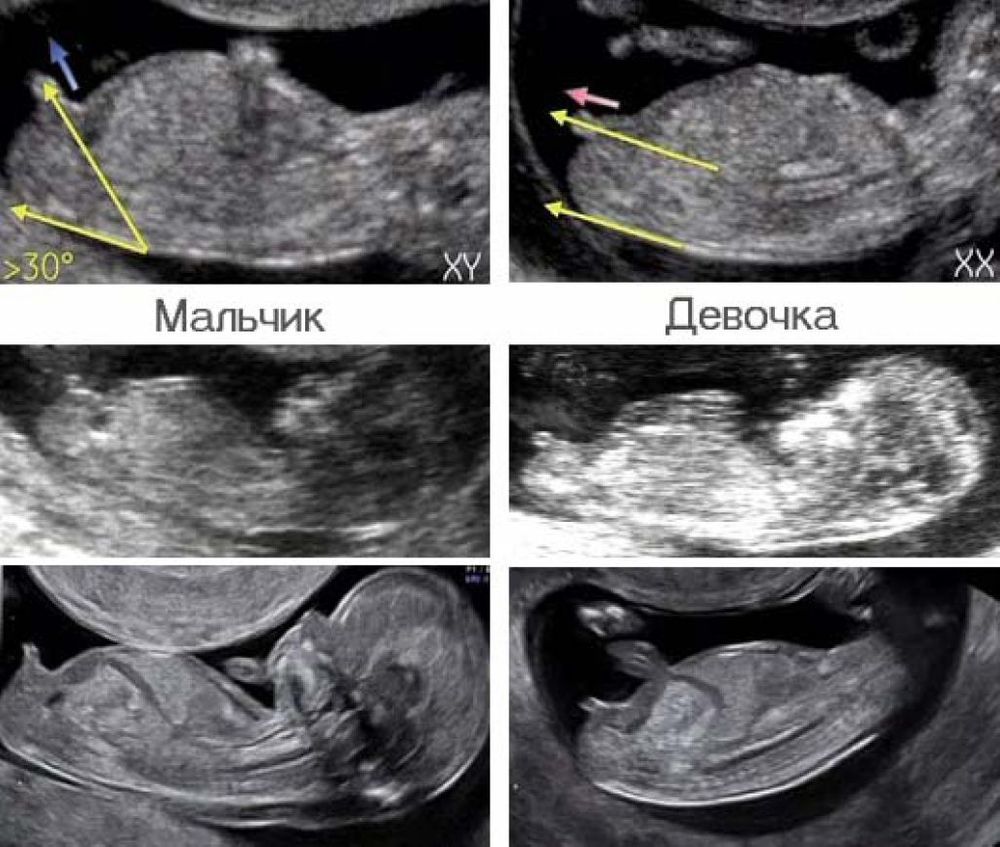

Мамедова Гуля, это половой бугорок, но его в таком ракурсе на Вашем сроке не смотрят. Повторюсь, нужно фото плода в профиль, а у Вас как бы лицом, полубоком что ли)) По крайней мере, я так увидела. Нужно вот так. Изображение

Посмотрим пол?) Всем спасибо за дочку, но это сынок в итоге 19 недель и пол малыша